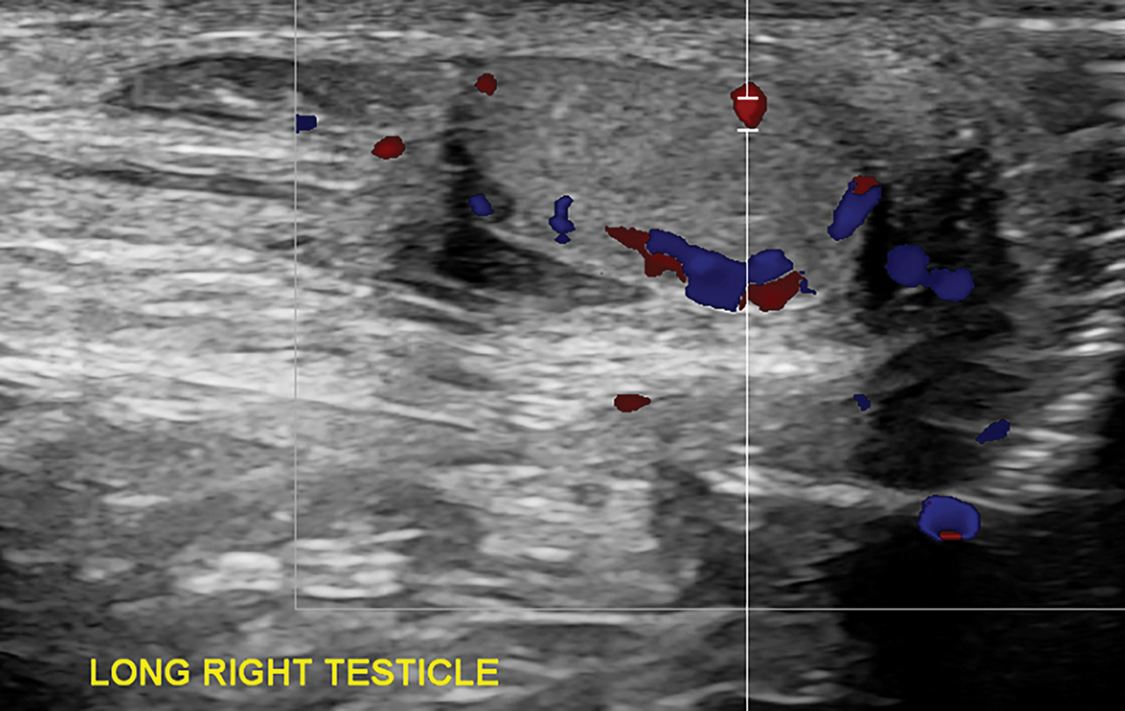

Pediatric Surgery was initially consulted due to concern for an incarcerated inguinal hernia. Point-of-care bedside ultrasound of the left inguinal canal was performed by Pediatric Surgery, and the contents appeared consistent with bowel per their read. Bedside reduction was attempted without success; thus, he was taken to the operating room emergently with Pediatric Surgery for hernia reduction and repair. Time from preliminary diagnosis of incarcerated inguinal hernia to case start was approximately two hours. Diagnostic laparoscopy revealed a closed inguinal ring without hernia and a loculated cystic mass just adjacent to the left ring (Figure 2). The cystic mass was 4 cm × 2.7 cm × 2 cm and dusky red-grey in appearance, with brown hemorrhagic material adherent to the external surface. The structure did not have any association with the bowel. At this point, Pediatric Urology was consulted intra-operatively. Formal intra-operative scrotal ultrasound was obtained, which revealed the left testicle located in the left hemiscrotum without blood flow on color Doppler evaluation (Figure 3A). A large lobulated, multiseptated, complex avascular fluid collection was seen in the left inguinal canal without extension into the peritoneal cavity (Figure 3B). The right testis was retractile but appeared normal (Figure 4).

FIGURE 4. Ultrasound with Doppler highlighting the right testis with normal echotexture and blood flow